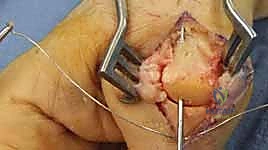

Before we make any incision, a thorough understanding of the intricate anatomy of the hand joints is paramount. This knowledge guides our dissection, protects vital structures, and informs our fusion strategy.

Neurovascular Considerations

A constant awareness of the neurovascular bundles is critical across all these joints. The proper digital nerves and arteries run along the lateral aspects of each digit, volar to the collateral ligaments. Dissection must be meticulous, staying dorsal and central when possible, and employing careful, blunt dissection laterally. Always consider the potential for nerve irritation or injury during hardware placement, especially K-wires, which can directly impinge on these structures if misplaced.

Patient Positioning and OR Setup

- Patient Position: The patient is typically supine on the operating table.

- Arm Positioning: The affected arm is placed on a radiolucent hand table, ensuring full access for the surgeon and unobstructed fluoroscopy. A pneumatic tourniquet is applied to the upper arm.

- Anesthesia: Regional block (e.g., axillary block) combined with sedation, or general anesthesia, is preferred.

- Sterile Prep and Drape: The entire hand and forearm are prepped and draped in a sterile fashion, allowing for full range of motion of the digits during positioning.